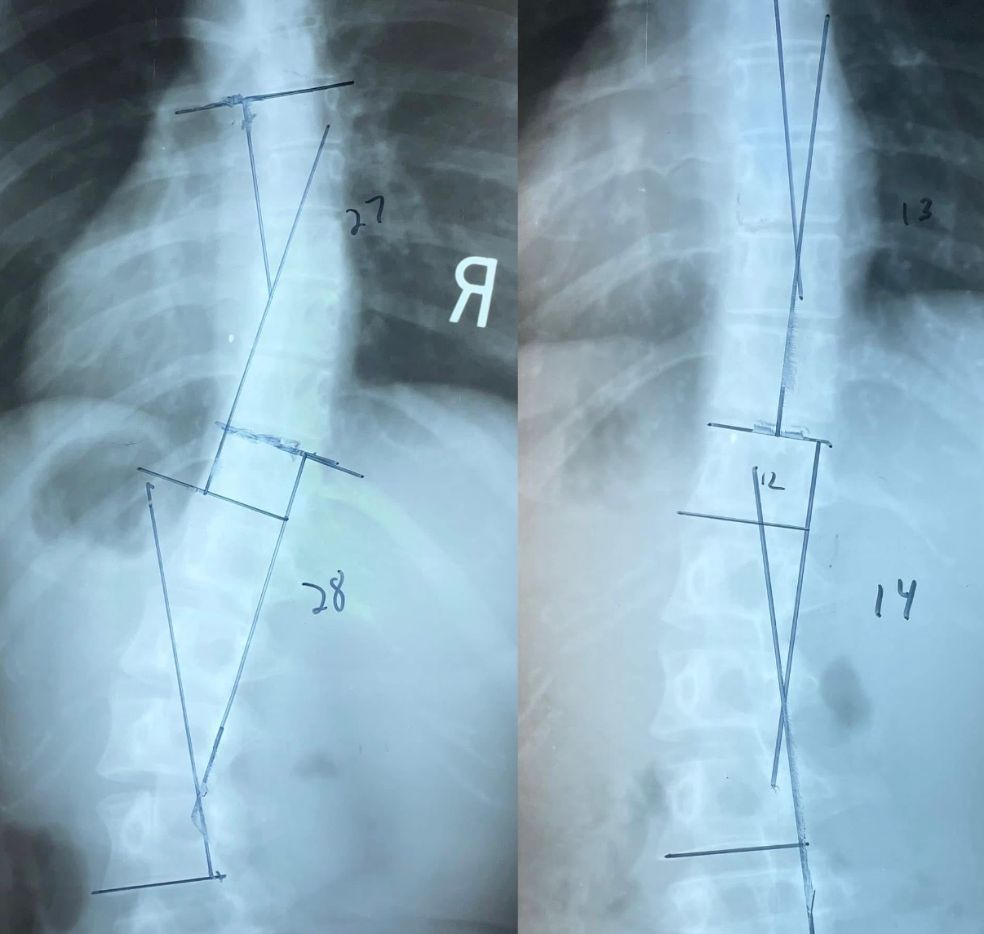

Before 27 Degrees

After 14 Degrees

28 Degrees

After

14 Degrees